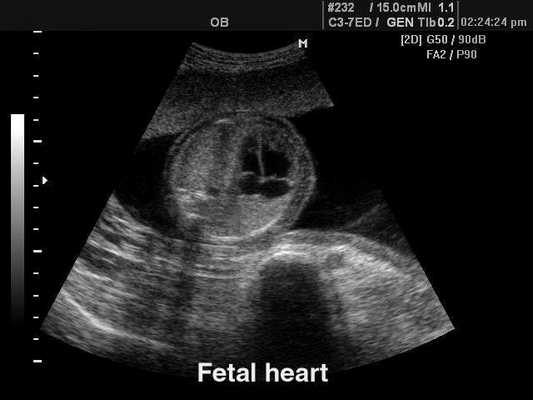

Сердце плода, B-режим

[EN] Эхограмма №122: Сердце плода в B-режиме.

Изображение получено с помощью УЗ сканера SonoAce-8000 (снят с производства).